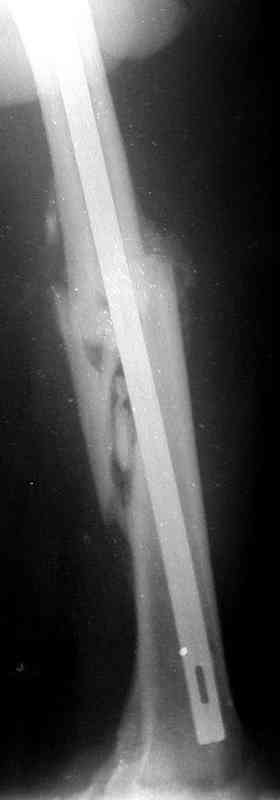

Уважаемые коллеги!На прилагаемых снимках - состояние после оперативного вмешательства (открытый перелом левого бедра в средней трети):

МОС, стержень нефиксированный. С момента операции прошло 8 месКак по Вашему мнению происходит консолидация? Допустимо ли смещение или необходима повторная операция по выравниванию конечности? Если да, какой метод рекомендуете (фиксированный стержень, пластина)?Буду благодарен за оперативный ответ.

Вы не пишете, есть ли сейчас болезненные проявления, и какие. Как пациент ходит. Какова функция колена. Ось выглядит приемлемо. Рентгенологически на сращение непохоже. Если есть клиника несращения (боль, хромота), то лучший выбор - закрыто рассверлить и перештифтовать блокированным гвоздем. Желательно определиться поточнее, нет ли проблемы с длиной , чтобы попутно и ее решить. И не создать. Ну и прежде всего исключить инфекцию. Если это инфицицированное несращение, план надо другой.

При таком диаметре штифта не удивительно, что перелом не сросся (кстати, какой диаметр и что за модификация штифта?).

Допустимо ли смещение...

В этой проекции угловое смещение градусов 15-20 - многовато будет. Есть ли укорочение?